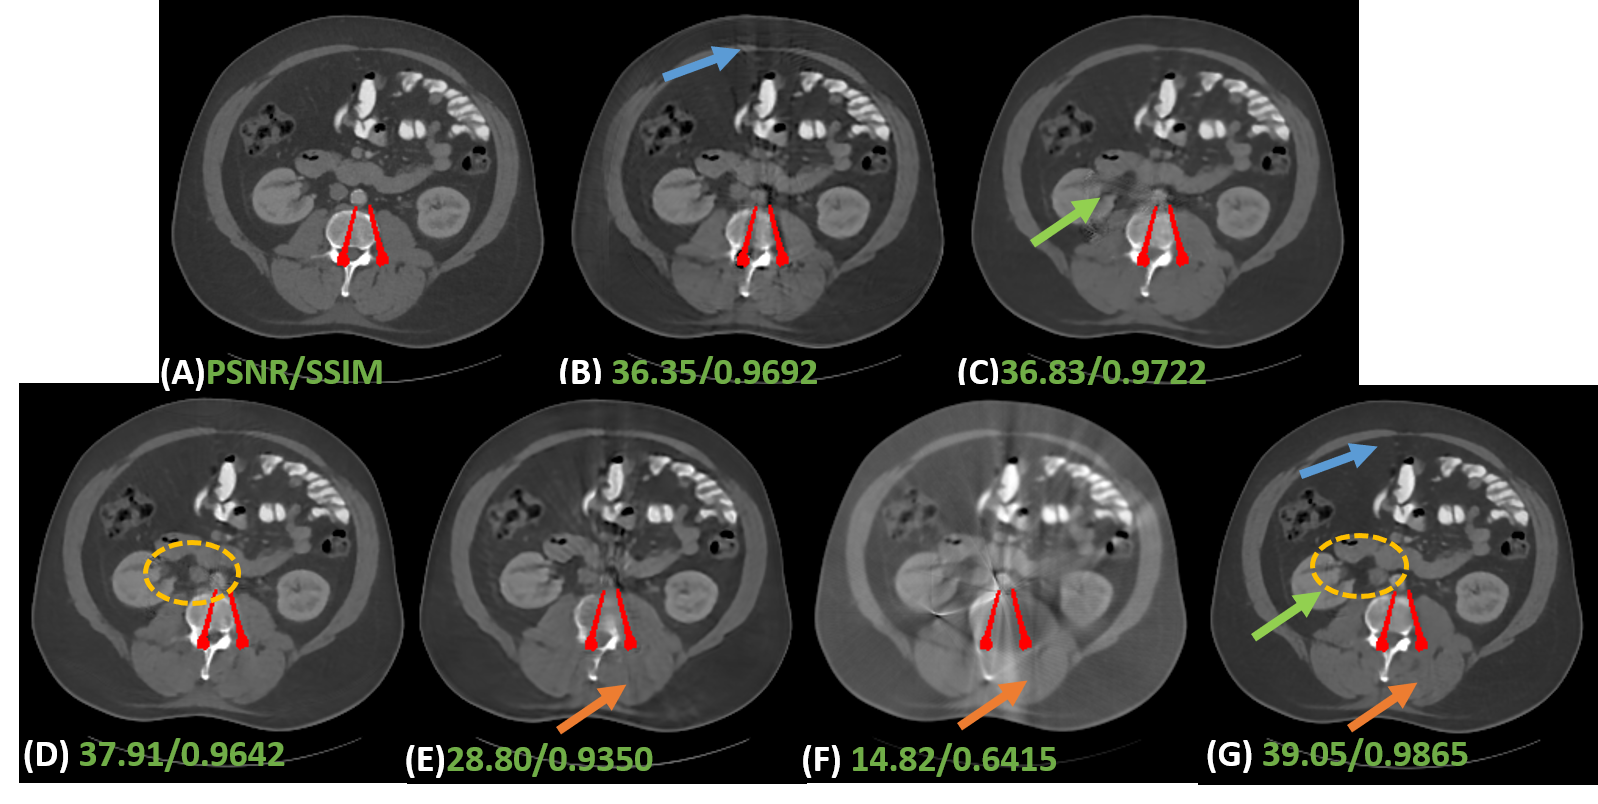

5.4 Experimental results on clinical data

To evaluate the robustness of our IDOL-Net for clinical practice, clinical CT images were tested and Fig. 7 shows the visual comparisons of one representative slice processed using different methods. The metal was segmented by the threshold of 2000 HU and the metal mask is painted in red for better visualization. The test image was normalized to the same range as the training data and the results were obtained using the model trained with simulated dataset used in the previous subsection. In Fig. 7 (A), the metal leads to severe artifacts, which covers some tissues, especially near the metal. It is observed that LI, NMAR and DuDoNet cannot retrieve the tissues around the metal, but due to the utilization of dual-domain information, DuDoNet outperforms most methods in artifact reduction. Since the shadow artifacts around the metal is very heavy, ADN cannot do much about this, which is similar to the situation in simulated dataset. It is observed that IDOL-Net suppresses most of the metal artifacts and effectively preserves the anatomical structures around the metals, which demonstrates its potential for real clinical application.

1) Effectiveness of prior estimation. Most dual-domain MAR methods usually use original or LI-interpolated sinogram and corresponding reconstructed CT images as inputs, or adopted LI’s corrected results as inputs. However, the first case results in incomplete artifact reduction and maintains some obvious artifacts in final corrected images. In addition, since LI is just a rough estimation, which gives rise to details lost around the metal. A possible solution is to generate both good quality prior sinogram and image. To investigate the effectiveness of the prior image and sinogram generated by our proposed disentanglement module, a network without this module, termed Refine-Net, is trained and we take metal-affected CT image and sinogram as inputs. Table 2 shows the quantitative results. It is clear to see that aided by prior image and sinogram, our model achieves much better score in terms of both metrics. As shown in In Fig. 8 (B), there are obvious artifacts indicated by a blue arrow.

2) Effectiveness of . There are two ways to obtain high quality prior image and sinogram. One is just predicting the clean data directly from contaminated data. The other is learning residual part and get the clean part by subtracting the learned residual data from original corrupted data. However, these methods may fail to separate the clean data or residuals from original data completely. In other words, there could be some useful information remaining in the restored data or residuals. To tackle this problem, inspired by disentangling representation, we learn both clean part and residual part simultaneously. In addition, we adopt to produce a lossless decomposition. To investigate the effectiveness of , we trained two networks, Clean-IDOL and Art-IDOL, without . It can be seen in Table 2 that both Clean-IDOL and Art-IDOL achieve lower SSIM and PSNR values than IDOL-Net. In Fig. 8, Clean-IDOL introduced secondary artifacts indicated by green arrow. Art-IDOL shows slight anatomic structure distortion marked by yellow dotted box. It is noticeable that the result of IDOL-Net is most consistent with the referenced image in all the methods.

3) Effectiveness of parallel branches. To show the effectiveness of our proposed interactive dual-domain parallel branches, we trained two networks, dubbed Prior-Im and Prior-Sino, which are only with image domain branch or sinogram domain branch, respectively. It can be seen in Table 2 that Prior-Sino gains lower SSIM and PSNR scores than other methods. The possible reason lies in that Prior-Sino restored projection data within metal trace region using the original contaminated data and the distortion introduced by inaccurate result will expand to the whole reconstructed image, which heavily lower both quantitative scores calculated in image domain. Prior-Im significantly improves the qualitative and quantitative results compared to Prior-Sino, but as shown in Table 2 and Fig. 8, our IDOL-Net have superior performance to Prior-Im, which provides impressive support for our claim that the proposed interactive dual-domain parallel branches are efficient.